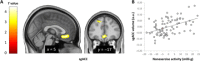

Physical activity substantially improves well-being and mental health, but the underlying brain processes remain unclear. Most research concerns exercise, although the majority of everyday human behaviors, such as walking or stair climbing, are nonexercise activities. Combining neuroimaging with ecological assessment of activity and GPS-triggered smartphone diaries, we show a specific association of nonexercise activity with energy in two independent samples mediated by the subgenual part of the anterior cingulate cortex (sgACC), a key emotion regulatory site. Furthermore, energy predicted a range of mental health metrics. sgACC volume moderated humans' emotional gain from nonexercise activity in real life: Individuals with low sgACC volume, a risk factor for depression, felt less energized when inactive but benefited more from periods of high nonexercise activity. This suggests an everyday life mechanism affecting affective well-being in the general population and, if substantiated in patient samples, a risk and resilience process for mood disorders.